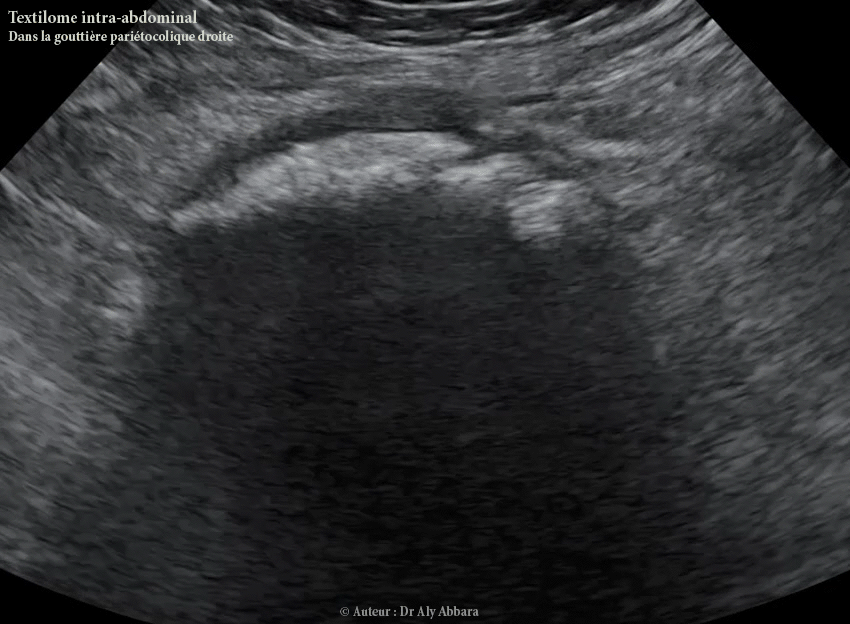

Textilome intra-abdominal occupant la gouttière pariéto-colique droite :

• L'échographie abdominale et l'IRM (Imagerie par Résonance Magnétique) abdominale montrent que ce textilome de découverte tardive (par rapport la date de la réalisation de césarienne) est enveloppé par une épaisse coque de tissu inflammatoire organisé (granulome) ; cette coque est à l'origine de l'enfouissement du textilome qui devient invisible et impalpable lors du premier temps de l'exploration chirurgicale de la cavité abdominale ; donc pour l'extraire il faut préalablement (par imagerie) parfaitement le localiser et connaître ses rapports anatomiques aux organes avoisinants (dans le cas présenté dans cet article : il s'agit du cæcum, du côlon ascendant, de la paroi abdominale latérale droite, de l'épiploon et des anses grêles).

• On remarque à l'échographie la constitution d'un cône d'ombre derrière la coque enveloppant le textilome, cette ombre est liée à l'épaisseur exagérée de cette coque inflammatoire (granulome).